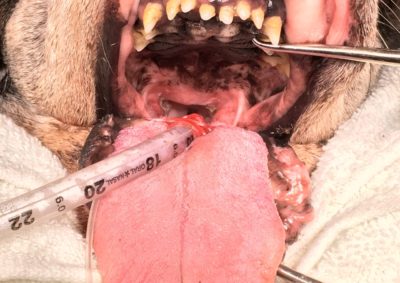

軟部組織外科

短頭種上部気道症候群〜ボストンテリア編〜

短頭種上部気道症候群(フレンチ編)